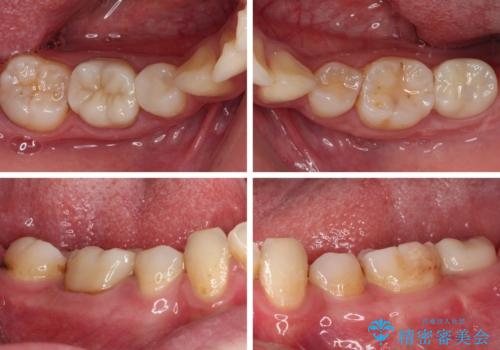

- 左下欠損部のインプラント治療と、右下の歯の痛みを気にして来院された患者様です。

左下の欠損部は、世界中で高い信頼を得ているストローマンインプラントを用いて治療を行うこととしました。

ただし、長期間欠損を放置していたことで、咬み合う上の奥歯が動いてしまっていたので、まずは上顎奥歯の部分矯正を行い、より理想的な咬み合わせを目指すこととしました。

右下の歯は、レントゲン上歯髄組織まで虫歯が及んでいるように見えましたが、痛みの症状は強くなかったため、歯髄組織の一部を断ち歯根部分の組織を保存する生活歯髄療法を第一選択に処置を進めて行くこととしました。

まず生活歯髄療法を行い、その後部分矯正やインプラント処置を行いましたが、最初の処置から1年以上経っても右下奥の処置歯の神経組織に異常は認められませんでした。

部分矯正を行ったことで、違和感のない咬み合わせを達成することができました。